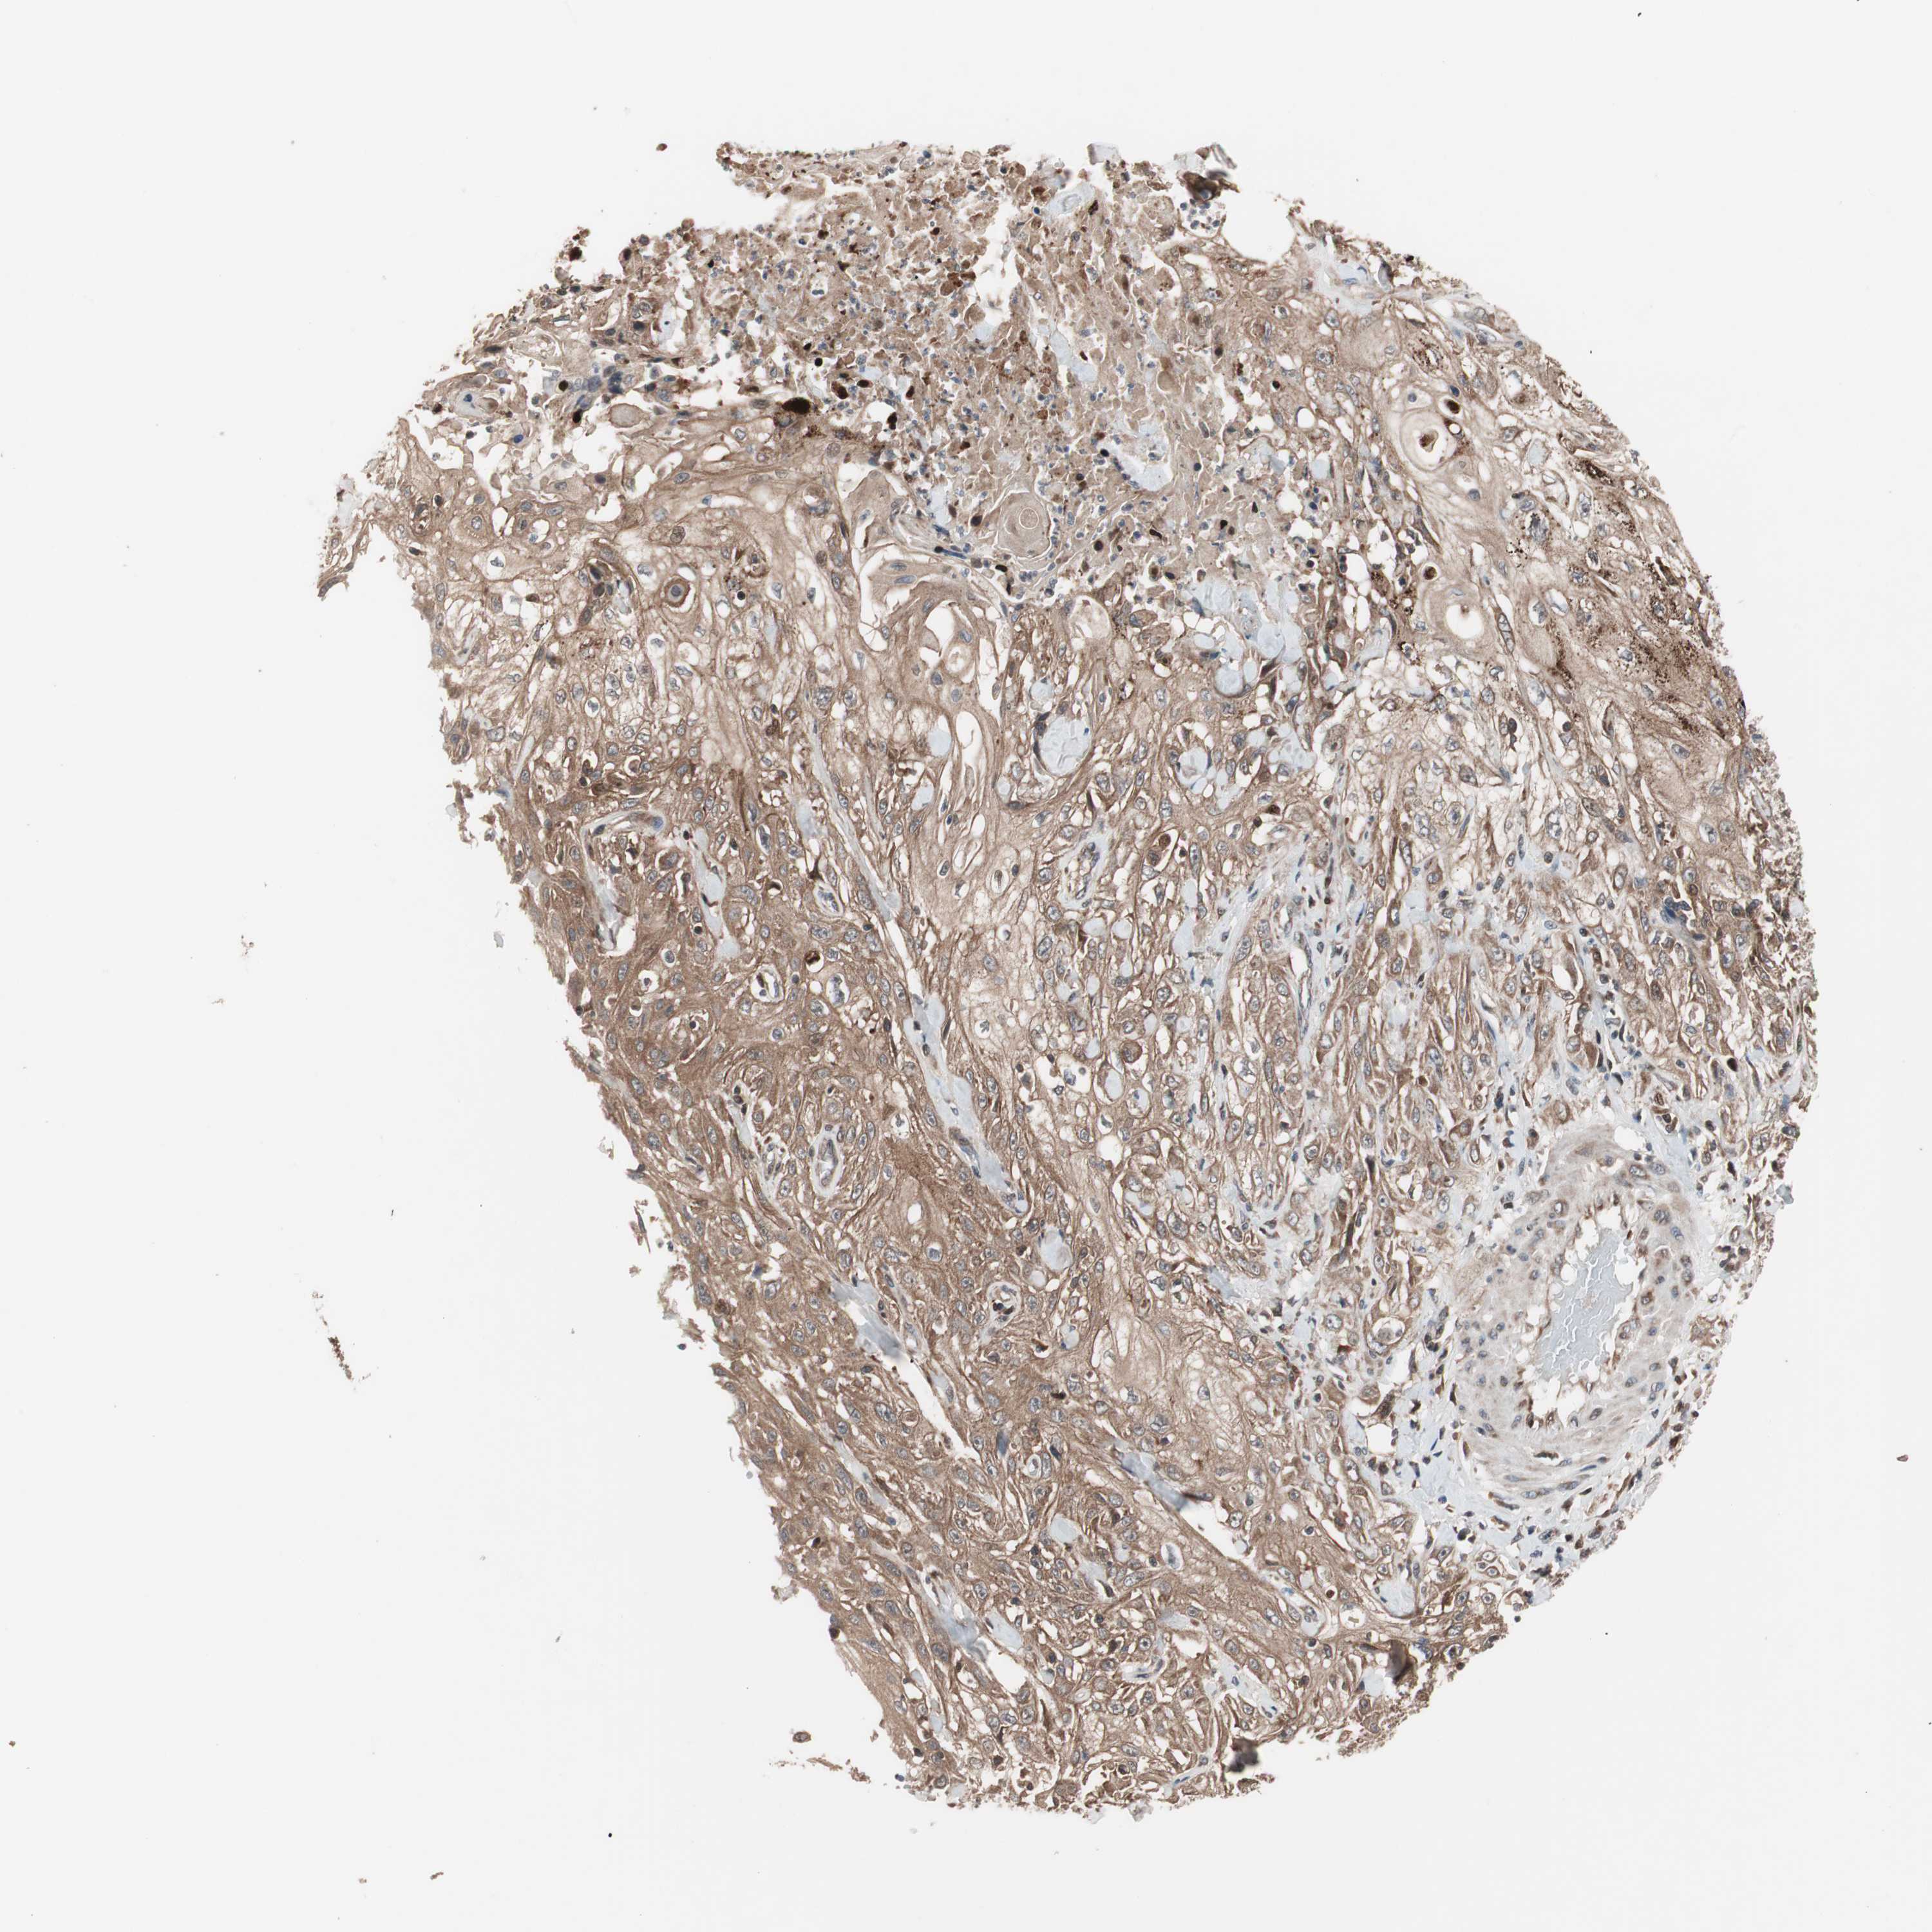

SKIN CANCER - Protein expressioni

A mouse-over function shows sample information and annotation data. Click on an image to view it in a full screen mode. Samples can be filtered based on level of antibody staining by selecting one or several of the following categories: high, medium, low and not detected. The assay and annotation is described here.

Antibody stainingi

Antibody staining in the annotated cell types in the current human tissue is reported as not detected, low, medium, or high, based on conventional immunohistochemistry profiling in selected tissues. This score is based on the combination of the staining intensity and fraction of stained cells.

Each image is clickable and will lead to virtual microscopy that enables deeper exploration of all samples and also displays staining intensity scores, fraction scores and subcellular localization as well as patient and tissue information for each sample.

Antibody HPA003097

Antibody CAB005385

Squamous cell carcinoma, NOS

Basal cell carcinoma

Squamous cell carcinoma, metastatic, NOS

Papilloma, NOS